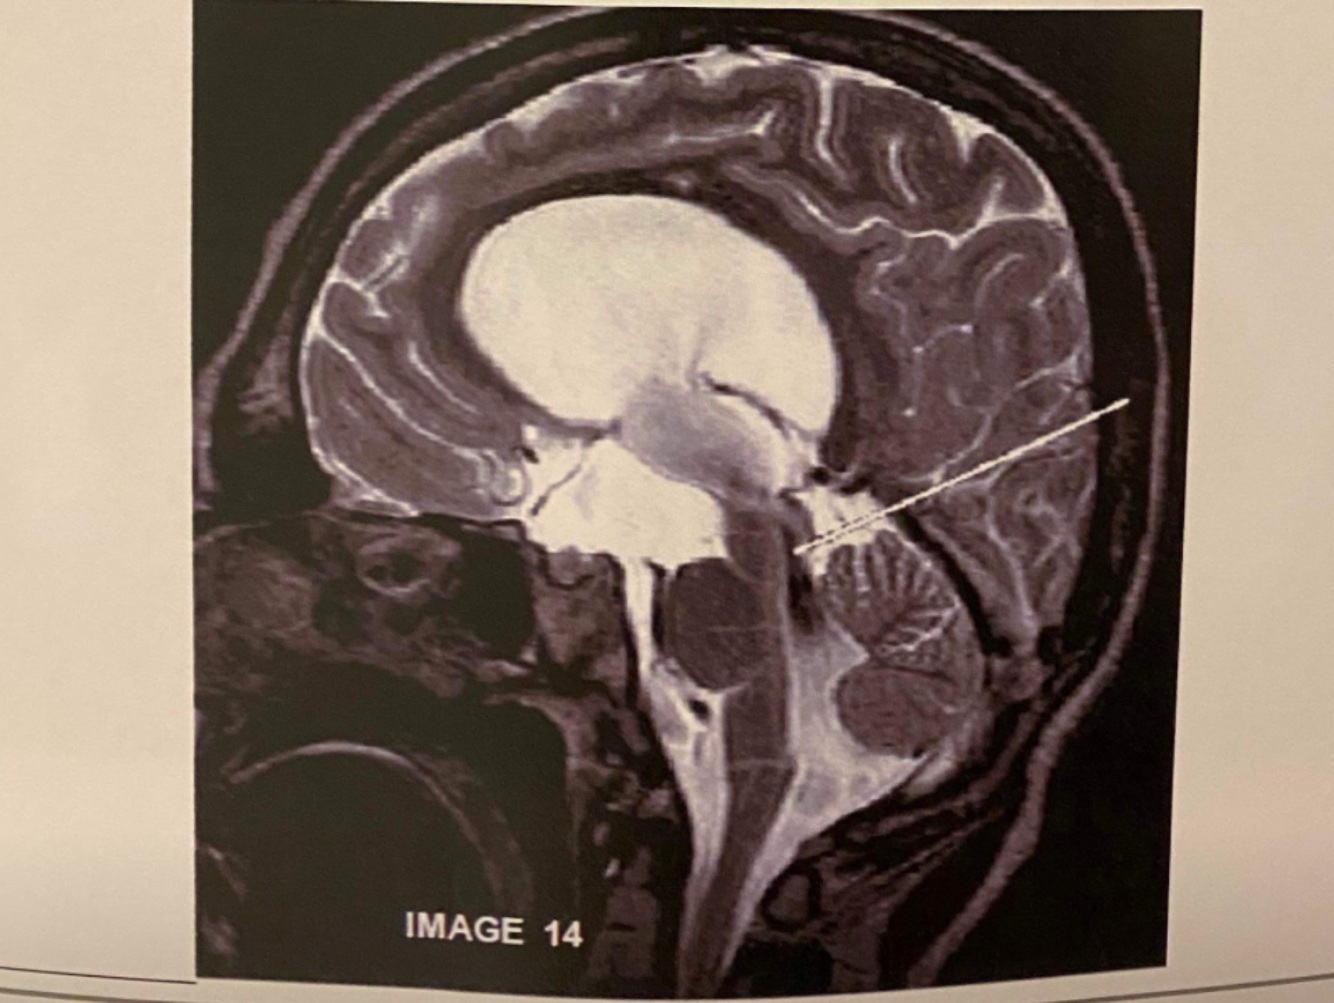

What is the artefact in this image caused by?

RF leak